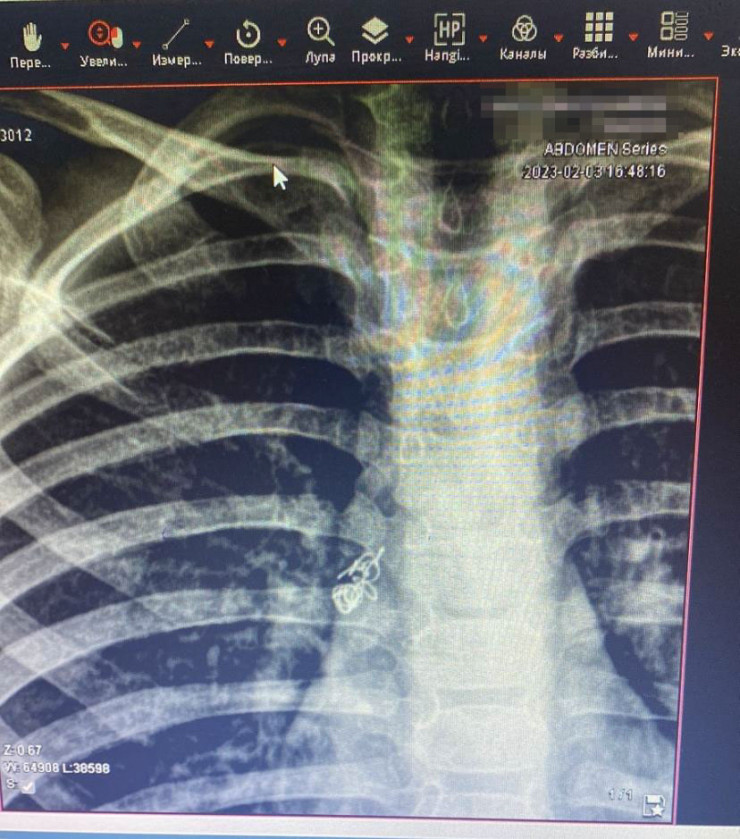

Алматинские врачи спасли ребенка, проглотившего пружинку от ручки Фото предоставлено пресс-службой ДГКБ №2 Алматы

8-летний мальчик жевал во рту пружинку от ручки и во время смеха вдохнул разжеванную пружинку, которая попала в дыхательные пути. Через некоторое время мальчик пожаловался на кашель и боль при дыхании. Ребенок был доставлен в приемный покой экстренной хирургии ДГКБ № 2.

"Ребенок осмотрен специалистами, проведена рентгенография грудной клетки. На рентгенограмме выявили инородное тело правого бронха. Он был госпитализирован, проведена подготовка к манипуляции. Под общим наркозом проведена жесткая трахебронхоскопия. Под визуальным контролем инородное тело (пружинка) обнаружено в правом главном бронхе", - сообщили в пресс-службе ДГКБ № 2.

Специальным зажимом "крокодил" пружина была удалена. Ребенка выписали из больницы через четыре дня.